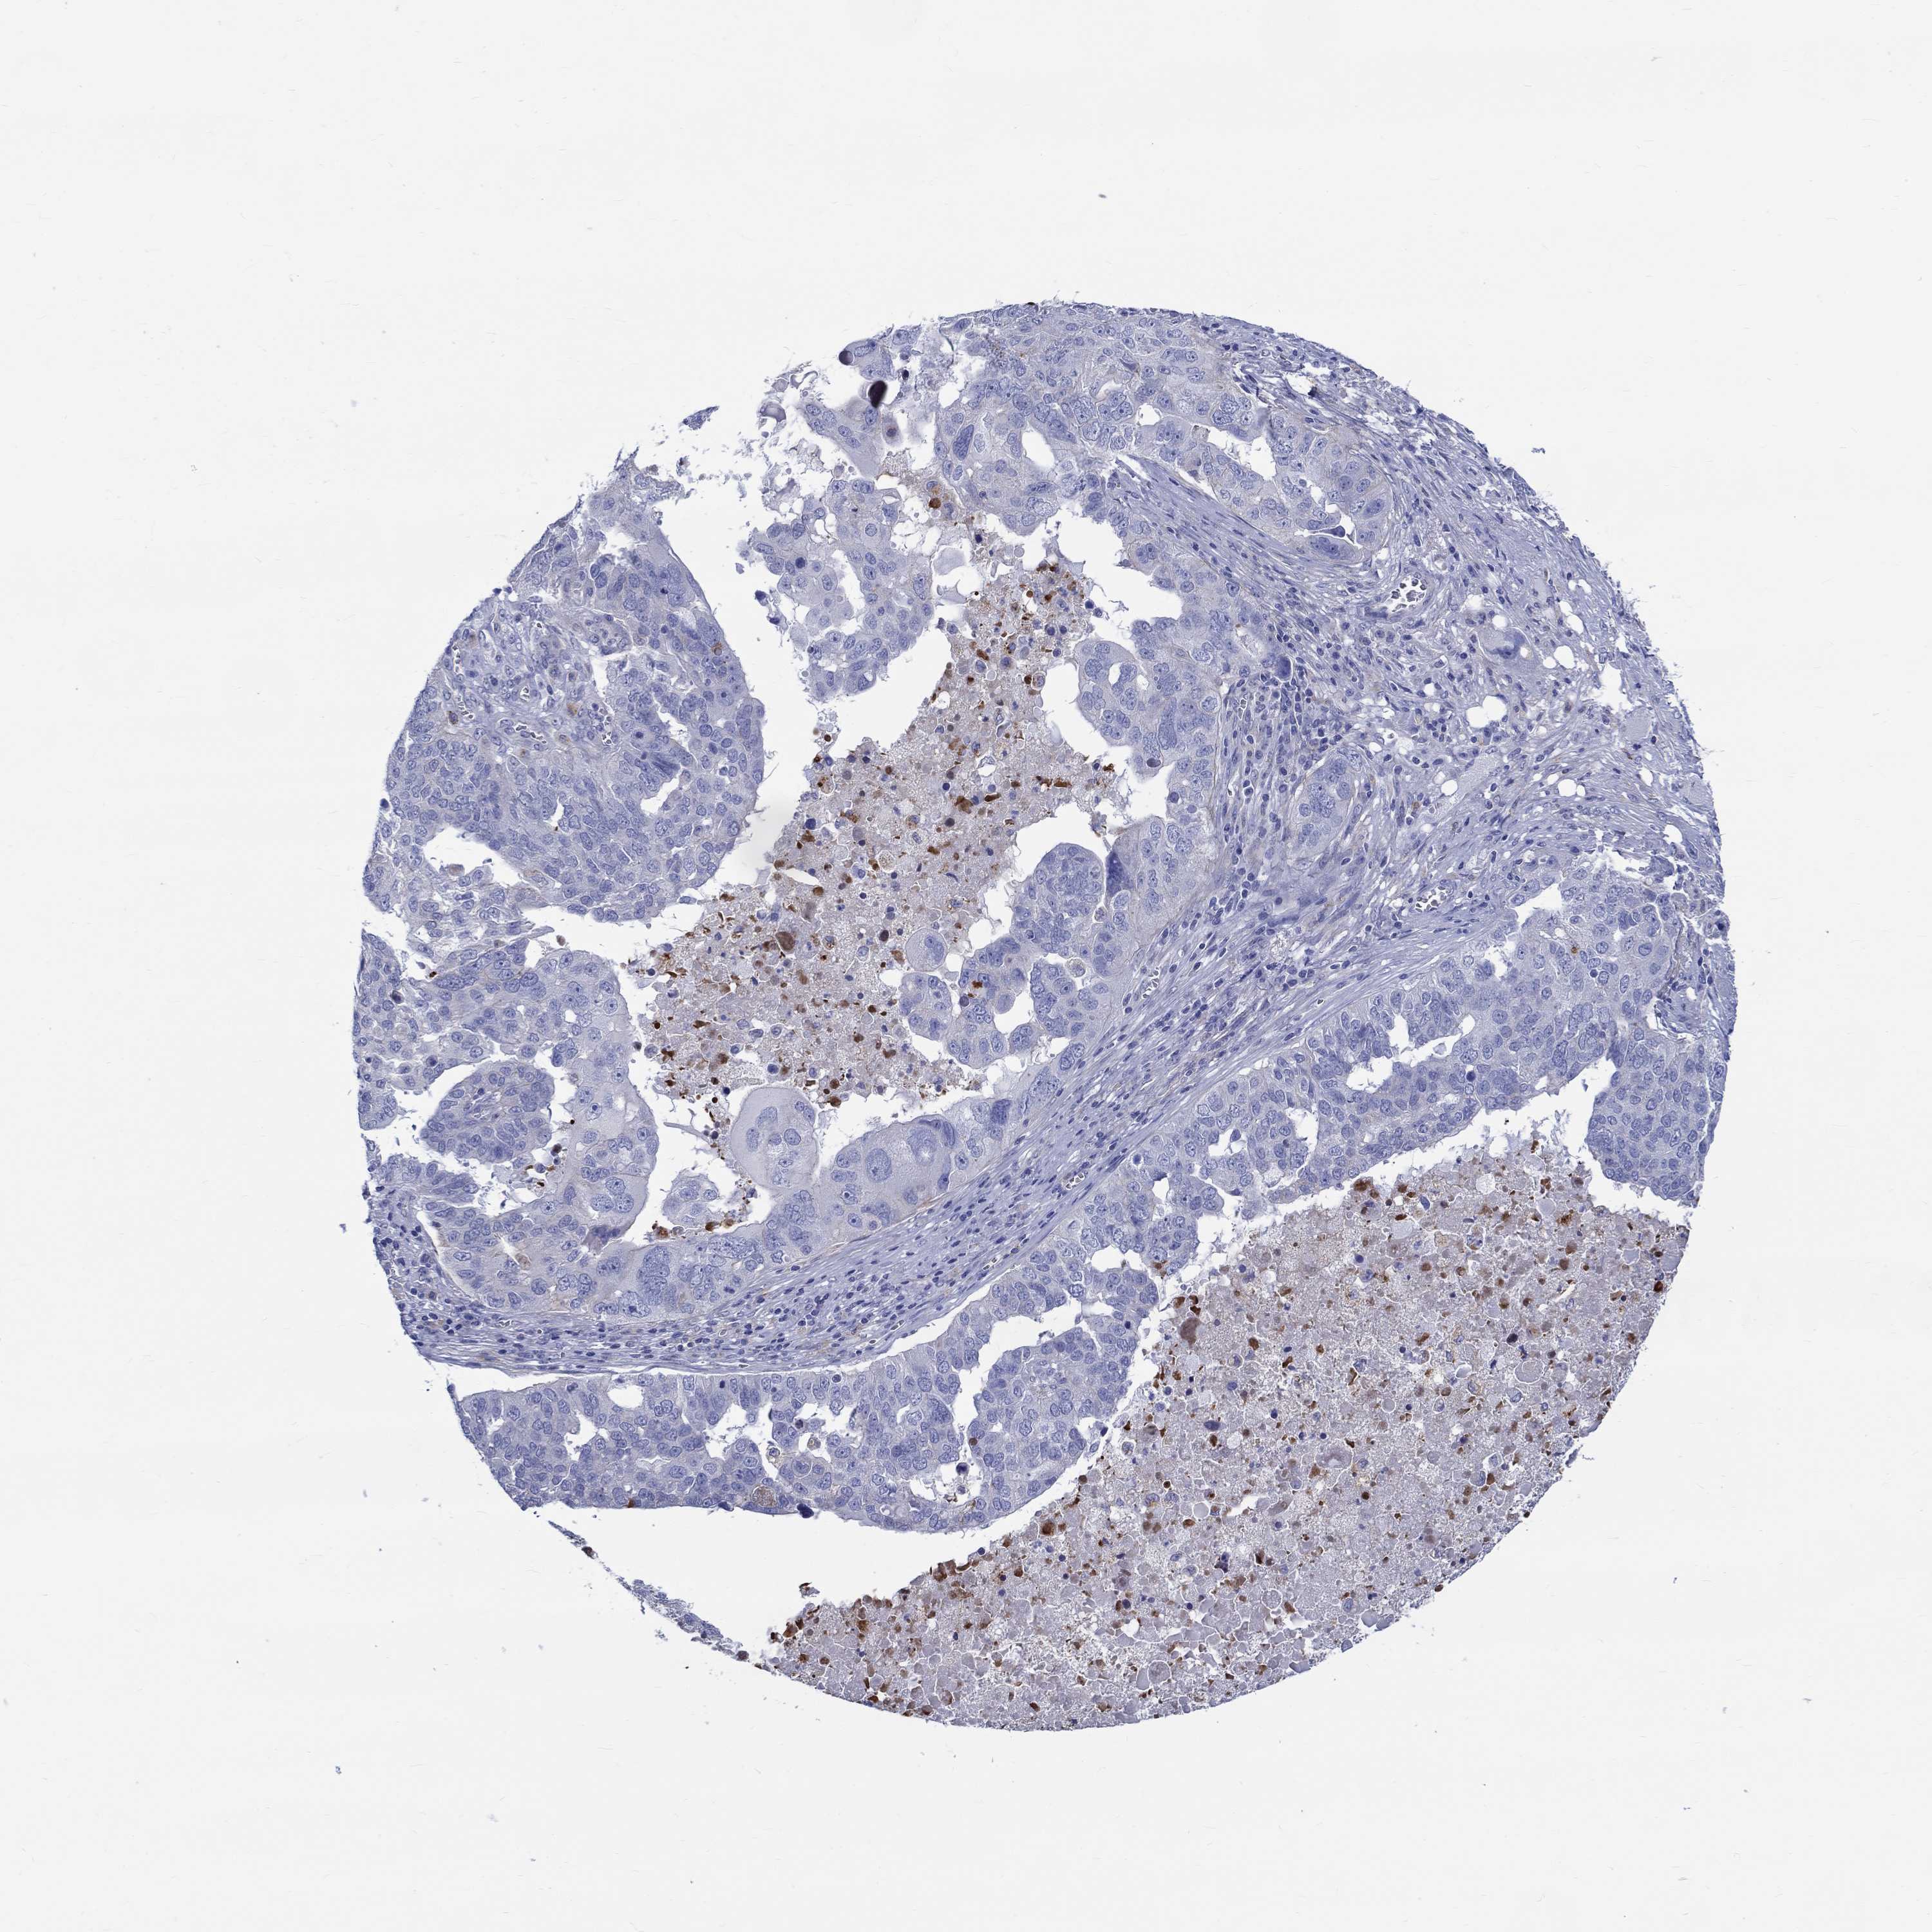

OVARIAN CANCER - Protein expressioni

A mouse-over function shows sample information and annotation data. Click on an image to view it in a full screen mode. Samples can be filtered based on level of antibody staining by selecting one or several of the following categories: high, medium, low and not detected. The assay and annotation is described here.

Note that samples used for immunohistochemistry by the Human Protein Atlas do not correspond to samples in the TCGA dataset.

Antibody stainingi

Antibody staining in the annotated cell types in the current human tissue is reported as not detected, low, medium, or high, based on conventional immunohistochemistry profiling in selected tissues. This score is based on the combination of the staining intensity and fraction of stained cells.

Each image is clickable and will lead to virtual microscopy that enables deeper exploration of all samples and also displays staining intensity scores, fraction scores and subcellular localization as well as patient and tissue information for each sample.

Antibody HPA076728

Staining

High

Medium

Low

Not detected

Intensity

Strong

Moderate

Weak

Negative

Quantity

>75%

75%-25%

<25%

None

Location

Nuclear

Cytoplasmic/membranous

Cytoplasmic/membranous,nuclear

Cystadenocarcinoma, serous, NOS

Cystadenocarcinoma, mucinous, NOS

Carcinoma, endometroid